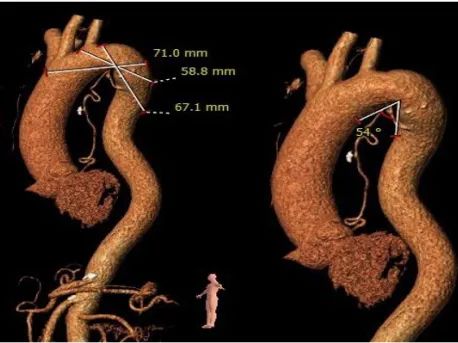

CT结果显示,患者为三叶式主动脉瓣,轻度钙化,瓣叶明显增生肥厚但未见明显融合,结合瓣上结构和左室流出道结构特点,较大可能影响瓣膜植入后的形态及贴壁性,存在瓣膜向下位移的风险,且大概率需要使用瓣中瓣策略完成手术。在瓣膜尺寸的选择上要更为精准,在瓣膜释放时,释放位置更要把握好。该患者还存在弓部夹角锐利,弓部宽度较短,且降主动脉扭曲,极大地考验了器械输送系统的过弓性能。

三叶式主动脉瓣, 瓣叶明显增厚,未见明显融合粘连,瓣叶钙化较低,假体瓣膜锚定难度较高,存在瓣膜位移风险,瓣中瓣风险偏高。

双侧股动脉管径尚可,主动脉弓部夹角锐利(54°)、弓部宽度较短(最短处仅58.8mm),降主动脉轻度扭曲,输送器过弓、跨瓣难度较高。